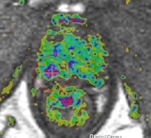

A 69-year-old male three years post electron-beam radiation therapy (EBRT, primary PC: Gleason 4+3 right PZ) with PSA increase to 2. MRI and TRUS-guided biopsy of this area confirmed Gleason 4+4 recurrence at right PZ (old tumor location). Left: Axial T2-weighted MR image shows low signal prostate due to previous EBRT. Therefore, tumor (arrow) is difficult to see. At arrow, there is some "bulging" (PI-RADS 5). Center: Axial DCE-MRI shows increased focal asymmetric contrast leakage at right PZ (circle, PI-RADS 5). Right: Axial ADC-map of DWI-MRI shows restriction (low signal, circle, PI-RADS 5). Final diagnosis: PI-RADS 5. TRUS biopsy of this area confirmed Gleason 4+4 recurrence.

A 69-year-old male three years post electron-beam radiation therapy (EBRT, primary PC: Gleason 4+3 right PZ) with PSA increase to 2. MRI and TRUS-guided biopsy of this area confirmed Gleason 4+4 recurrence at right PZ (old tumor location). Left: Axial T2-weighted MR image shows low signal prostate due to previous EBRT. Therefore, tumor (arrow) is difficult to see. At arrow, there is some "bulging" (PI-RADS 5). Center: Axial DCE-MRI shows increased focal asymmetric contrast leakage at right PZ (circle, PI-RADS 5). Right: Axial ADC-map of DWI-MRI shows restriction (low signal, circle, PI-RADS 5). Final diagnosis: PI-RADS 5. TRUS biopsy of this area confirmed Gleason 4+4 recurrence."Prostate imaging at 3-tesla benefits from higher signal-to-noise ratio and enables high-quality imaging within a short time without the use of an ERC [endorectal coil]. Data on 3-tesla for prostate cancer MRI are still conflicting. Thus, further research on this topic is needed," the authors noted. "Limitations of 3-tesla MRI are shorter T2- and longer T1-relaxation times, problems with susceptibility artifacts, dielectric effect, specific absorption rate, and the homogeneity of the magnetic field. However, hardware, multichannel coil, and parallel imaging technique improvements are currently solving most of these problems."